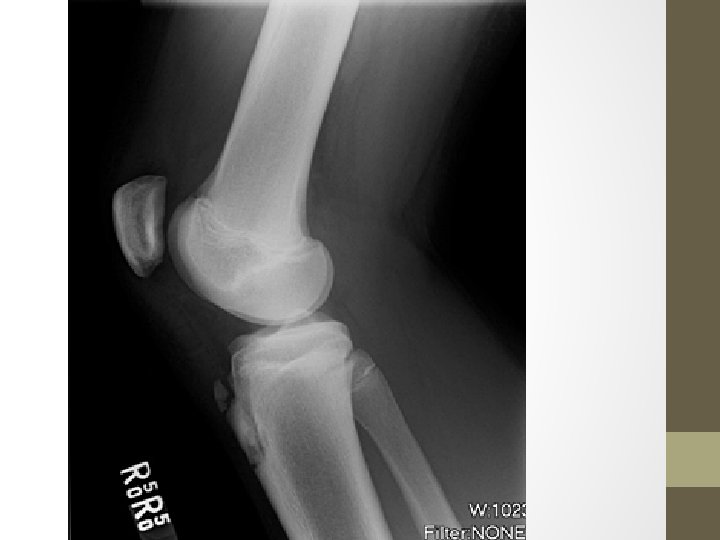

• Fizik muayenede tibial tüberkül üzerinde şişlik ve hassiyet mevcuttur. • Diz ekstansiyonu veya çömelme ağrıyı arttırabilir. • Hamstring ve quadriseps kasları gergindir. • Radyografi tanısal değildir, diğer ağrı nedenlerini dışlamak için yardımcı olur. • Patellar tendonda kalsifikasyon ve kalınlaşma, tibial tüberkülde düzensiz kemikleşme ve üstteki yumuşak dokuda şişlik görülebilir.